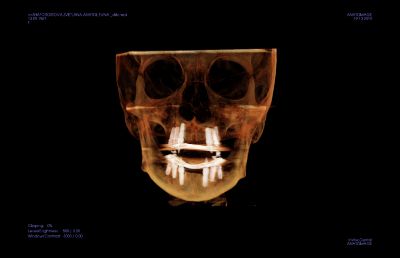

Этап 1. Подготовка

На этапе подготовки к реализации протокола  вам сделают общие анализы крови, а также конусно-лучевую томографию (КЛКТ), которая необходима для определения оптимальных мест для размещения имплантов в челюсти. На основе снимка КЛКТ в специальной программе вам составят цифровой диагностический план вашего лечения.